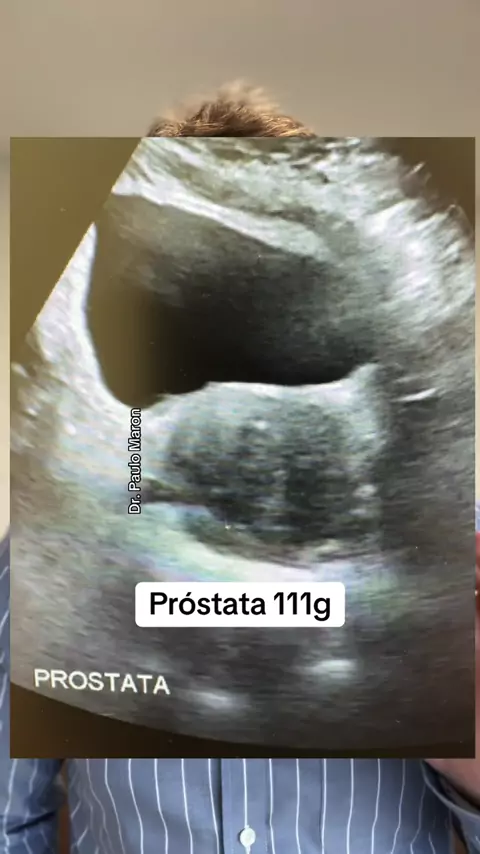

Dr. Paulo Maron - Urologista

Próstata de 111g #prostataaumentada #hiperplasiaprostatica #holep